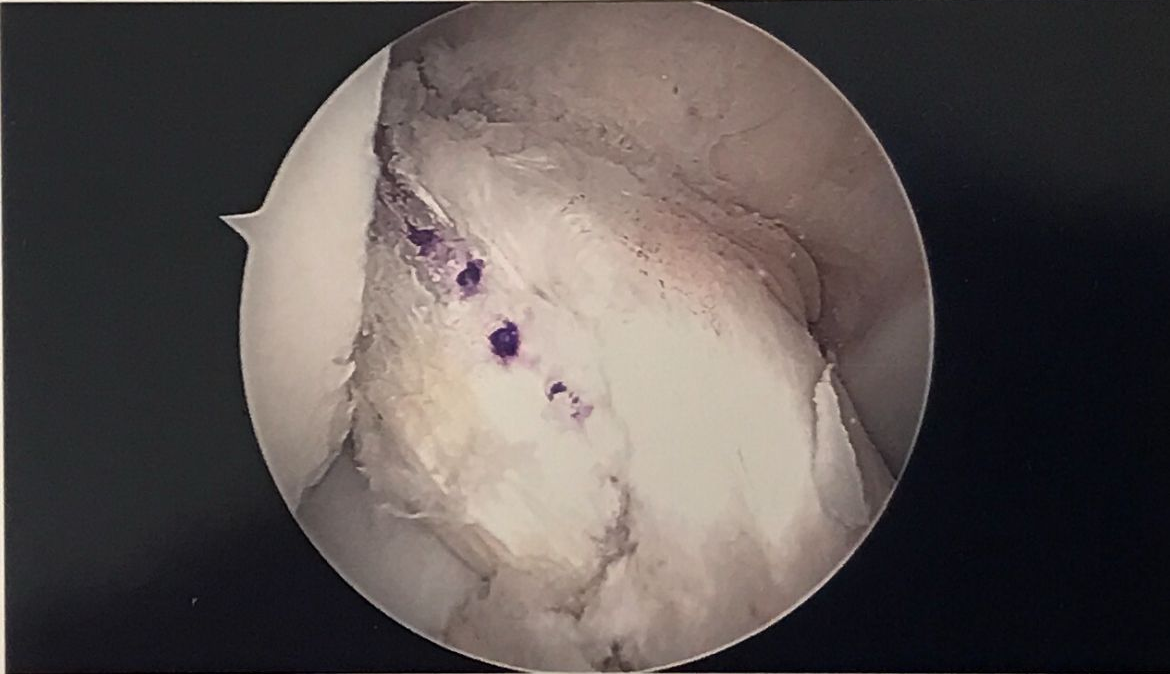

ACL Injury

Treatment options are tailored to the patient’s injury spectrum and their individual expectations of return to sports and activities. Non-operative treatment of ACL injuries can be as effective as operative treatment dependent on a number of factors.

There is excellent evidence to show that operative treatment of ACL disruption, coupled with a comprehensive rehabilitation programme, can enable individuals to return to their previous level of sport.